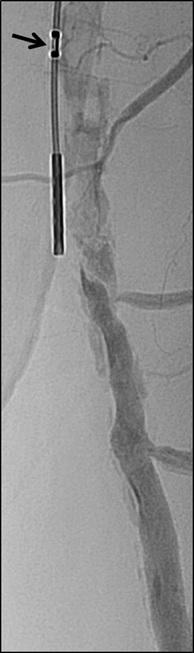

Specialist clinic brings IVC filter innovation into focus

William T Kuo is an interventional radiologist based at Stanford University (Stanford, USA), where he holds a professorship. He spoke to Interventional News about his prize-winning work in the field of advanced inferior vena cava (IVC) filter retrieval— he earned the Cardiovascular and Interventional Radiological Society of Europe’s (CIRSE) Award for Excellence and Innovation in Interventional Radiology (IR) in 2022—and also took the opportunity during the interview to leave aspiring physicianinnovators with some words of wisdom.

What inspired your specialisation in advanced IVC filter retrieval and your invention of excimer laserassisted removal in particular?

I became intrigued by vena cava filters during medical school, and soon began studying everything I could about them including their creative invention, beautiful geometry, crucial function, and evolution. To me, they represented the intersection of art, science, biomedical engineering, and medicine. During my IR training, I enjoyed deploying, and especially removing, these devices which seemed straightforward at first, but I soon realised the retrieval process was not always simple.

In training, I helped develop and publish a wire-loop method to remove tilted filters, and this inventive process was something I really enjoyed. After joining my academic group, I discovered a growing number of patients suffering from problems related to indwelling filters. Although we wanted to offer more help, we soon exhausted all of our retrieval methods, and hardly anyone wanted to see these filter patients in clinic.

Traditional teaching was that filters could be left implanted as permanent devices, and I remember being advised to focus on something else, but I could not turn my back on these patients whose suffering inspired me to do better. I began to wonder if it would be possible to reverse the ‘permanent’ interactions that had formed between the organic vessel and artificial implant, perhaps on a cellular/molecular level.

The vena cava is a thin-walled vessel prone to injury, but through our early histologic analyses, we began to appreciate how a distinct layer of fibrotic tissue consistently formed along the filter attachment sites. I began searching for something that could be precise in this location, and that is when I discovered excimer laser. Rather than burning or cutting, the excimer laser adds just enough energy to disrupt the molecular bonds of surface tissue—a useful property that can remove very fine layers of organic

material without impacting underlying tissues. At 308nm wavelength, I hypothesised that excimer laser had the potential to perform 50–100 micron ablation along fibrotic tissue planes surrounding an IVC filter while sparing the native vessel wall.

Interestingly, a group in Japan had attempted excimer laser application within the canine IVC, but they quickly abandoned their experiments after noting significant vessel injury. However, I believed their results were limited due to the shorter-term dwell times (insufficient fibrotic layer) in their animal model versus the histopathology results I had observed in our human data derived from long-term filter implants. This knowledge, along with a sense of urgency in dealing with a rising epidemic of filter-related complications, gave me the confidence to bypass further animal testing and proceed with excimer laser use in humans.

Our inaugural patient travelled 2,000 miles to reach our centre in Stanford; and he became the first human to undergo successful laser-assisted filter retrieval. During the trial, which spanned nearly a decade, we accepted many high-risk cases and encountered some complications, but fortunately these were treatable. We learned from our mistakes while continuously honing our techniques to improve safety; and ultimately, we discovered that a variety of embedded filters previously considered irretrievable could now be safely removed using excimer laser, regardless of dwell time. Many patients could finally be alleviated from their filter-related morbidity or spared the risk of developing such complications.

What have been the highlights of the 10+ years since you first performed this procedure?

Looking back, the requests from our early patients to find solutions that did not yet exist was inspirational, so the main highlight has been developing a patient-inspired procedure to improve the lives of many others. Establishing a first-in-man clinical trial in conjunction with a dedicated IVC Filter Clinic has also been gratifying. It has been an honour to meet and touch the lives of so many patients from around the country and around the world. Sharing this knowledge with our trainees, clinical teams, and early adopters has been rewarding; and seeing our results eventually confirmed across multiple centres was validating. Based on our collective data, the excimer laser sheath was finally cleared by the US Food and Drug Administration (FDA) as the first ever device approved for advanced filter removal.

What led you to set up the Stanford IVC Filter Clinic?

When I began my career, patients with embedded IVC filters came to us because they had no other place to go. In 2010, filter-related complications were acknowledged as an emerging health problem when the US FDA issued a Filter Safety Alert urging all physicians caring for patients with filters to consider removing the filter as soon as protection from pulmonary embolism is no longer needed. Other health agencies and societies soon followed with similar guidelines. However, despite this heightened awareness and improving follow-up, many filters still could not be removed using standard methods, especially after prolonged implantation, subjecting patients to all the risks and anxiety of living with a permanent implant. For all these reasons, I decided to launch the Stanford IVC Filter Clinic dedicated to helping these patients.